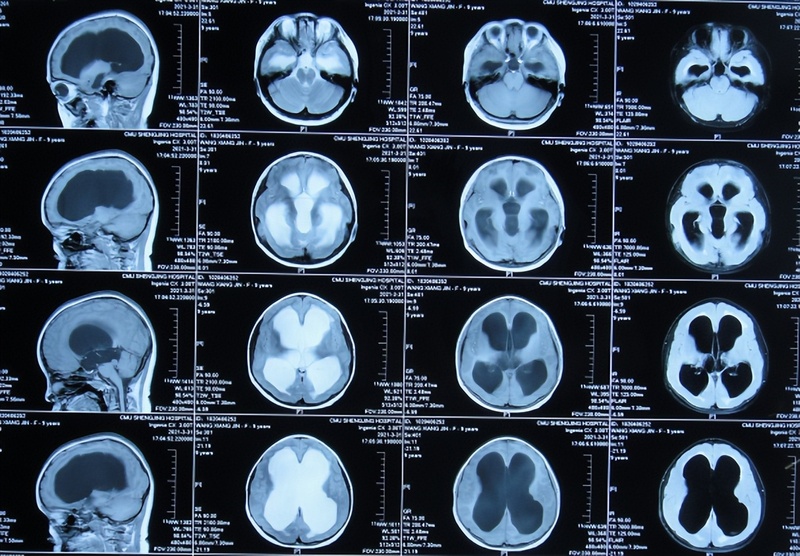

腦積水分流術(shù)后嚴(yán)重并發(fā)癥:腦嚴(yán)重坍陷,發(fā)熱、意識喪失,全身木僵,肢體震顫,雙腳呈“芭蕾舞腳”,李小勇腦脊液科治后蹦蹦跳跳健康出院患者女,9歲,遼寧省東港市人。一、李小勇腦脊液科入院前病史患兒于2021年3月26日,意外從樓梯摔下,當(dāng)時只見臉上有輕傷,未做特殊處理;但次日出現(xiàn)頭痛且呈持續(xù)進(jìn)行性加重,2天后即2021年3月29日,到第1家遼寧省東港市某東港醫(yī)院就醫(yī),查頭顱CT示腦室廣泛擴(kuò)張(片子丟失)。為治療腦積水,次日即2021年3月30日,住入第2家遼寧省沈陽市某省級三甲醫(yī)院神經(jīng)外科,住院次日查頭顱CT示腦積水(圖-1)。圖-1:2021年3月31日頭顱CT住院第2天即2021年4月1日,進(jìn)行了腦室腹腔分流術(shù),壓力為1.0。術(shù)后次日查頭顱CT示腦室分流術(shù)后狀態(tài),腦室有所縮?。▓D-2)。圖-2:2021年4月2日頭顱CT住院治療10天即2021年4月9日出院,出院時頭痛消失。第1次出院后35天即2021年5月14日(腦室腹腔分流術(shù)后44天),再次到給予手術(shù)的醫(yī)院復(fù)查,查頭顱CT示雙側(cè)慢性硬膜下血腫,腦室受壓變?。▓D-3);但因無不適癥狀,只調(diào)整了分流泵壓力為1.5。圖-3:2021年5月14日頭顱影像第1次出院后48天即2021年5月27日(腦室腹腔分流術(shù)后57天),因出現(xiàn)頭痛嘔吐,在家附近的醫(yī)院復(fù)查頭顱CT示硬膜下血腫進(jìn)一步增多,腦室受壓變?。ㄆ觼G失)。第1次出院后52天即2021年5月31日(腦室腹腔分流術(shù)后61天),第2次住院給予手術(shù)的醫(yī)院;入院后第2天即2021年6月2日,進(jìn)行了雙側(cè)硬膜下血腫鉆孔引流術(shù),引流出暗紅色液體,引流術(shù)后次日查頭顱CT示雖兩側(cè)硬膜下血腫明顯減少,但腦室有擴(kuò)張(圖-4)。圖-4:2021年6月3日頭顱CT第2次住院治療3天即2021年6月5日,復(fù)查頭顱CT右側(cè)硬膜下血腫基本消失,左側(cè)少量殘留,但腦室較前增大(片子丟失),頭痛嘔吐消失。第2次住院治療9天即2021年6月11日(腦室腹腔分流術(shù)后72天),醫(yī)生建議出院,出院時雖活動正常,頭痛嘔吐消失,但表情僵硬,言語變少。第2次出院11天即2021年6月22日(腦室腹腔分流術(shù)后83天),又出現(xiàn)頭痛嘔吐,次日即2021年6月23日,第3次到給予手術(shù)的醫(yī)院,查頭顱CT示左側(cè)硬膜下血腫再次明顯增多(片子丟失),當(dāng)天進(jìn)行了第2次左側(cè)硬膜下血腫鉆孔引流術(shù),引流出暗紅色,術(shù)后當(dāng)天查頭顱CT示左側(cè)硬膜下血腫明顯減少,但腦室仍擴(kuò)張(圖-5)。圖-5:2021年6月23日頭顱CT第3次住院2天即2021年6月25日,患兒變得不能言語,肢體活動變差,查頭顱CT和腹壁CT分別示硬膜下血腫減輕但腦室擴(kuò)張,分流管腹腔端被包裹(片子丟失);檢查后當(dāng)天進(jìn)行了腹腔探查分流管調(diào)整術(shù)。腹腔探查分流管調(diào)整術(shù)后第1天,患兒癥狀有短暫好轉(zhuǎn),能簡單言語,肢體活動有所恢復(fù),但之后癥狀再次持續(xù)變差。腹腔探查分流管調(diào)整術(shù)后第2天即2021年6月27日,出現(xiàn)間斷發(fā)熱,最高體溫39度左右,肺部CT示肺炎(片子丟失),給予靜脈滴抗生素治療。腹腔探查分流管調(diào)整術(shù)后第3天即2021年6月28日,雖體溫有下降,但進(jìn)食變困難,留置胃管。腹腔探查分流管調(diào)整術(shù)后第4天2021年6月29日,仍間斷發(fā)熱,復(fù)查頭顱CT示腦室有變小,但雙側(cè)仍有少量硬膜下積液(圖-6)。圖-6:2021年6月29日頭顱CT盛京腹腔探查分流管調(diào)整術(shù)后8天即2021年7月3日,體溫變正常,但變得意識不清,出現(xiàn)左側(cè)肢體抽搐,口服德巴金后無改善。在該院第3次治療10天左右,癥狀不見好轉(zhuǎn)且持續(xù)加重,無奈下家屬網(wǎng)上查詢確認(rèn)后找到北京的李小勇腦脊液科。二、李小勇腦脊液科治療過程和結(jié)果2021年7月4日(腦室腹腔分流術(shù)后95天反復(fù)出現(xiàn)硬膜下積液,腦室擴(kuò)張)轉(zhuǎn)住入李小勇腦脊液科。入院時:間斷發(fā)熱體溫38度左右,意識喪失,雙眼不能睜閉眼,眼神呆滯,不能遵囑活動,不能言語,不能經(jīng)口進(jìn)食,留置胃管,全身木僵、肢體震顫,雙腳呈“芭蕾舞腳”(圖-7)。圖-7:2021年7月4日入院時入院當(dāng)天查頭顱CT示腦室分流術(shù)后仍腦積水,硬膜下血腫(腦塌陷)(圖-8),考慮堵管。圖-8:2021年7月4日頭顱CT入院后次日即2021年7月5日,拔除了原腦室腹腔分流管+腦室外引流術(shù),術(shù)中發(fā)現(xiàn)腦室端分流管被粘連包裹(圖-9);術(shù)后當(dāng)天查頭顱CT示腦室引流術(shù)后腦室有縮?。▓D-10)。圖-9:2021年7月5日頭顱CT腦室外引流術(shù)圖-10:2021年7月5日堵管粘連治療2天即2021年7月6日,引流出的腦脊液呈淡粉色渾濁(圖-11)。圖-11:2021年7月6日治療15天即2021年7月19日,間斷發(fā)熱變基本正常,引出的腦脊液色變清亮(圖-12)。圖-12:2021年7月19日治療21天即2021年7月25日,病情好轉(zhuǎn)為:意識變清,看到搞笑的視頻能笑出聲音,但仍不能說話(圖-13)。圖-13:2021年7月25日治療25天即2021年7月29日,右手遵指令能顫抖的且緩慢的抬起,且引流出的腦脊液變完全透明清亮(圖-14)。圖-14:2021年7月29日治療30天即2021年8月2日,進(jìn)行了腦室腹壁外引流術(shù)。治療33天即2021年8月5日,變得能經(jīng)口進(jìn)食米糊,體溫已變正常20余天(圖-15)。圖-15:2021年8月5日治療44天即2021年8月16日,查頭顱CT示腦室縮小,還有點(diǎn)硬膜下血腫(圖-16)。圖-16:2021年8月16日頭顱CT治療58天即2021年8月30日,查頭顱核磁(圖-17)后,繼續(xù)抗感染治療。圖-17:2021年8月30日頭顱核磁治療74天即2021年9月15日,已拔出胃管,進(jìn)食基本正常,左手能不自主抬起,但手抖的厲害,但情緒變得煩躁,一直喊叫(圖-18);查頭顱CT后(圖-19),繼續(xù)抗感染治療。圖-18:2021年9月15日圖-19:2021年9月15日頭顱核磁因腦積水分流術(shù)后并發(fā)癥(堵管,顱內(nèi)感染)病情較為嚴(yán)重,患兒在李小勇腦脊液科繼續(xù)治療2個月半,病情又再開始繼續(xù)好轉(zhuǎn)。2021年12月2日(治療153天),意識變完全清楚,情緒穩(wěn)定,飲食變完全正常(體重較入院時增加),肢體震顫消失;右手能按指令伸出相應(yīng)的手指;變得能睜閉眼睛了(圖-20)。圖-20:2021年12月2日治療166天即2021年12月15日,雙腿變的能遵指令抬起,睜閉眼仍慢些(圖-21);例行查頭顱CT示腦室引流狀態(tài),未見異常(圖-22)。圖-21:2021年12月15日圖-22:2021年12月15日頭顱CT治療186天即2022年1月4日,病情大幅度好轉(zhuǎn)為:四肢遵命活動均變快,睜閉眼也變快,能遵囑慢慢的張嘴伸舌頭,扶著能坐起活動(圖-23)。圖-23:2022年1月4日治療207天即2022年1月25日,在攙扶下能下地邁步走路,但后腳跟不能著地,腳仍呈“芭蕾舞腳”,言語交流變基本正常(圖-24)。圖-24:2022年1月25日治療228天即2022年2月15日,攙扶下走路右腳后跟變得能著地了(圖-25)。圖-25:2022年2月15日治療243天即2022年3月3日,走路進(jìn)一步變好,家長扶著一側(cè)就能走(圖-26)。圖-26:2022年3月3日治療250天即2022年3月10日,變得能自己走路了,稍不穩(wěn),還能聲情并茂的朗讀電子書(圖-27)。圖-27:2022年3月10日在腦脊液各項(xiàng)化驗(yàn)均達(dá)標(biāo)后于2022年3月16日,進(jìn)行了腦室腹腔分流術(shù)(圖-28)。圖-28:2022年3月16日頭顱CT2022年3月29日(李小勇腦脊液科治療269天),患兒被治療正常健康的狀態(tài)出院。出院時:精神很好,走路基本正常,還能蹦跳,還能單腿站立左腿稍差,說話稍差(圖-29);出院時頭顱CT示未見異常(圖-30)。圖-29:2022年3月29日出院圖-30:2022年3月28日出院時頭顱影像三、出院后隨訪出院后1個月即2022年4月,家屬發(fā)來視頻,肢體活動已變完全正常(能跑、能蹦,還能跳),且說話也變得好很多基本正常(圖-31)。圖-31:2022年4月出院后2個月即2022年5月,家長再次發(fā)來視頻:身體各項(xiàng)已完全恢復(fù)至正常的健康的狀態(tài),時常鍛煉身體跳風(fēng)靡全網(wǎng)的“毽子操”,說話變也完全正常(圖-32)。圖-32:2022年5月